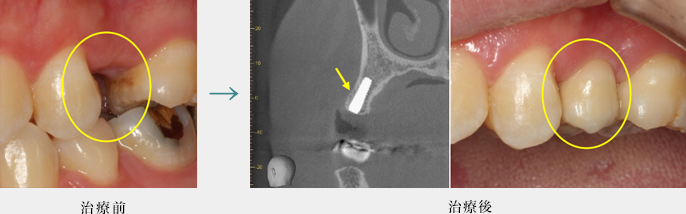

挺出による歯の保存

差し歯の中で虫歯が生じ、歯茎の深部まで虫歯が進行していました。

このままでは歯を作れないので、矯正によって歯を上方に牽引し、歯茎の中から健康な歯質を出しました。

インプラント

インプラントは歯を失った部位の骨の中にチタン製の人工の歯根を埋入する治療法です。

メリットは自分自身の歯のように咬めること、周りの歯を削ることなく治療ができることです。

デメリットは外科処置が必要になること、治療期間と費用の負担があることがあげられます。